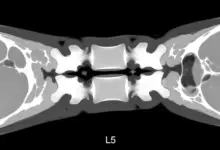

A espondilolistese displásica é um escorregamento congênito entre as vértebras, mais comum em L5 S1.

É um tipo de listese de origem congênita. As facetas articulares nascem orientadas de forma anômala, o arco posterior pode comprimir a cauda equina e a translação entre L5 e S1 tende a ocorrer ao longo do crescimento.

- Tomografia, útil em dúvidas anatômicas e planejamento cirúrgico.